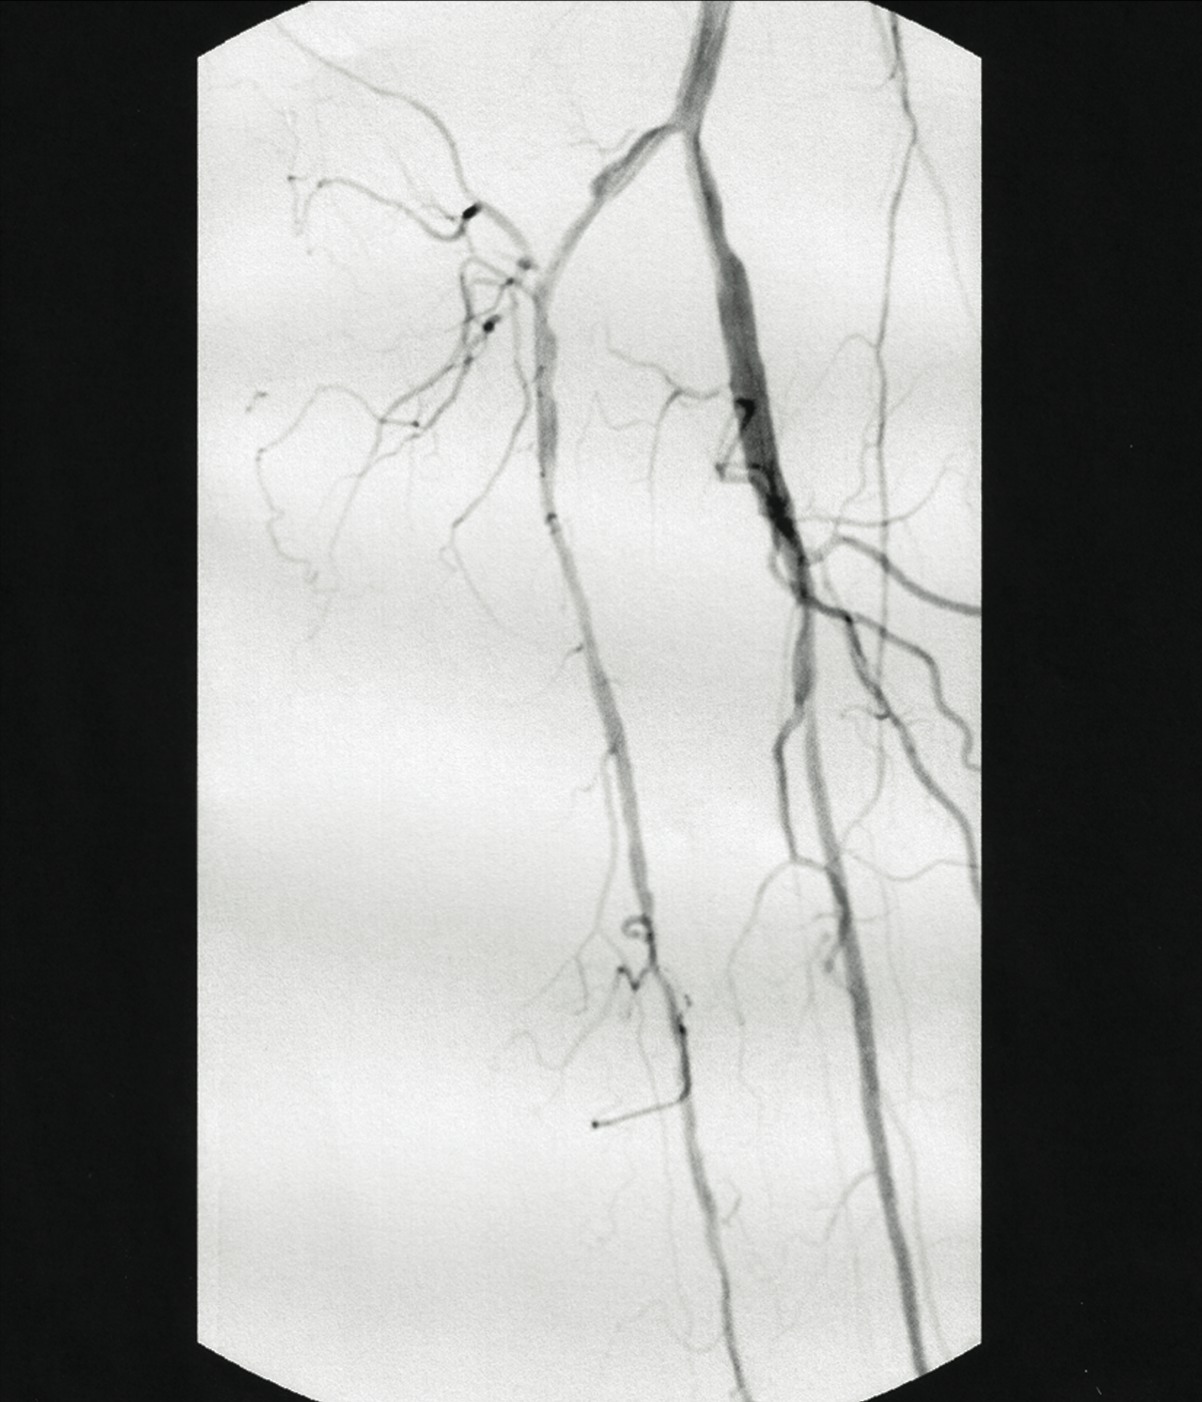

In one case study, a 69-year-old male was referred to a lower extremity limb salvage clinic with severe painful claudication and ulceration. He had prior amputation of the hallux and second digit of the right foot secondary to gangrene, and a prior endovascular angioplasty of the anterior tibial artery. He was scheduled for a below-knee amputation at another facility. His past medical history included diabetes mellitus for eight years, hypertensive cardiovascular disease and chronic renal failure, which initially required dialysis and eventually led to a right orthotopic kidney transplant. The patient history also included monocular blindness in the right eye. The patient was a former smoker who quit 30 years ago. His family history was significant for diabetes mellitus maternally and morbid obesity. He did have night cramps and reproducible leg pain with ambulation. His medications included Medrol, Cellcept, Prograf, Avandia, Zocor, Ambien, Atenolol, aspirin and insulin. He denied any known allergies. In regard to the physical exam, the patient’s vital signs were stable. His blood pressure was 137/84, his pulse was 80, respirations were 14 and his temperature was 98.5ºF. His pain was seven out of 10 on the visual analogue scale (VAS). His random blood sugar (RBS) at three hours postprandial was 131 mg/dL. The vascular exam revealed non-palpable pulses to the right lower extremity. The title= After delivering the catheter to the lesion, one would position it at the selected treatment area and switch the driver on. Switching the driver on automatically deflects the catheter tip, lifts the cutter and activates the motor. Doppler exam revealed a non-Dopplerable posterior tibial artery and a weakly monophasic dorsalis pedis artery. The distal foot was cool to the touch with elevated capillary refill time. An open ulcer was present at the prior amputation site of the first and second digits with gangrenous changes present. His right ankle-brachial index (ABI) was 0.69. Previous vascular intervention results included a balloon angioplasty of the right anterior tibial artery. His prior angiogram revealed a 100 percent occlusion of the posterior tibial artery and 75 percent stenosis of the proximal anterior tibial and fibular arteries. We referred the patient to a cardiovascular interventionalist for immediate vascular evaluation. The patient underwent a selective abdominal aortogram, which revealed severe infrapopliteal disease bilaterally. The posterior and anterior tibial arteries are 100 percent occluded proximally. The peroneal artery was patent and supplied collateral arterial circulation to the distal anterior and posterior tibial arteries. The patient underwent endovascular intervention including laser atherectomy, Silverhawk endovascular atherectomy and balloon angioplasty of the anterior tibial artery. The patient required a transmetatarsal amputation (TMA) after the Silverhawk procedure but avoided the need for a significant proximal amputation. There were no complications while healing the TMA. He exhibited no further complications 12 months after the endoscopic atherectomy.